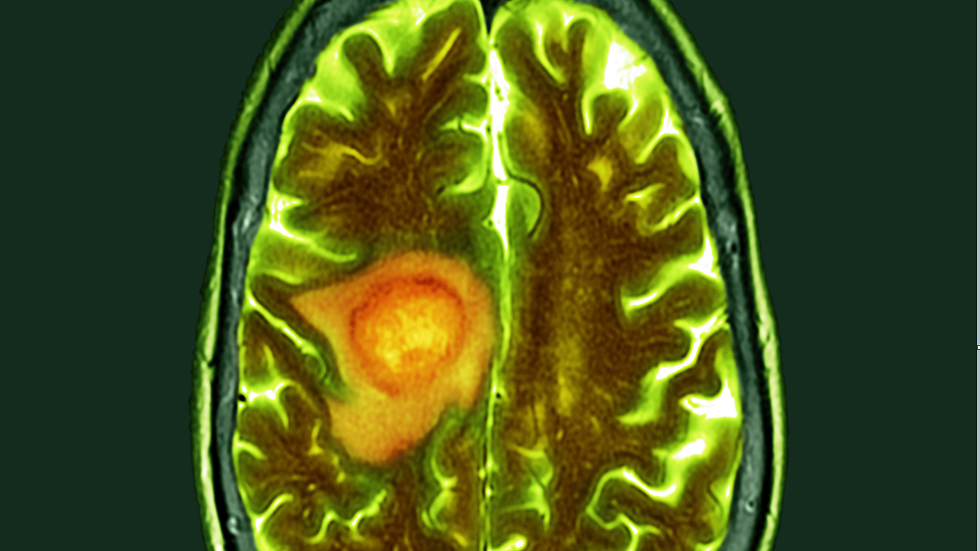

عامل يسرع تطور سرطان الدماغ

اكتشف علماء معهد نارا للعلوم والتكنولوجيا الياباني أن النشاط غير الطبيعي لجين Shootin1b يساعد خلايا الورم الأرومي الدبقي (أورام الدماغ) على الانتشار بشكل أسرع عبر الأنسجة.

وتشير مجلة Advanced Science إلى أن الورم الأرومي الدبقي يعتبر أحد أكثر أنواع سرطان الدماغ عدوانية وفتكا. وغالبا ما يُشخَّص في مرحلة متأخرة، وتنتشر خلاياه بسهولة في جميع أنحاء الأنسجة، ما يجعل الاستئصال الجراحي وطرق العلاج الأخرى غير فعالة. لذلك، لا يتجاوز معدل البقاء على قيد الحياة لمدة خمس سنوات لمرضى الورم الأرومي الدبقي 5%.

وقد ركز الباحثون اليابانيون اهتمامهم على جين shootin1b، الذي يتحكم في حركة الخلايا. يساعد هذا الجين الخلايا المناعية على الحركة لتتمكن من الاستجابة للعدوى، لكن في خلايا الورم تنشط هذه الآلية بشكل غير طبيعي. ونتيجة لذلك، تتلقى خلايا الورم الأرومي الدبقي نوعا من "الجذب" يسمح لها بالتحرك بسرعة والاستيلاء على مناطق جديدة من الدماغ.

وأظهرت التجارب على الفئران أن بروتين Shootin1b يشكل "قبضات" جزيئية خاصة تربط الهياكل الداخلية للخلية ببيئتها، مما يحول الحركة داخل الخلية إلى قوة تدفعها للأمام. وهذه الآلية مثالية للانتشار السريع، وتجعل الورم شديد الخطورة.

ويقول البروفيسور إيناغاكي، المشرف على الدراسة: "من خلال تثبيط النشاط غير الطبيعي لـ shootin1b، يمكن إيقاف هجرة خلايا الورم الأرومي الدبقي وإبطاء تطور المرض. وقد يصبح هذا الجين هدفا علاجيا جديدا لعلاج سرطان الدماغ".

ووفقا للعلماء، قد يمهد هذا الاكتشاف الطريق لابتكار أدوية جديدة تعمل على منع حركة الخلايا السرطانية.